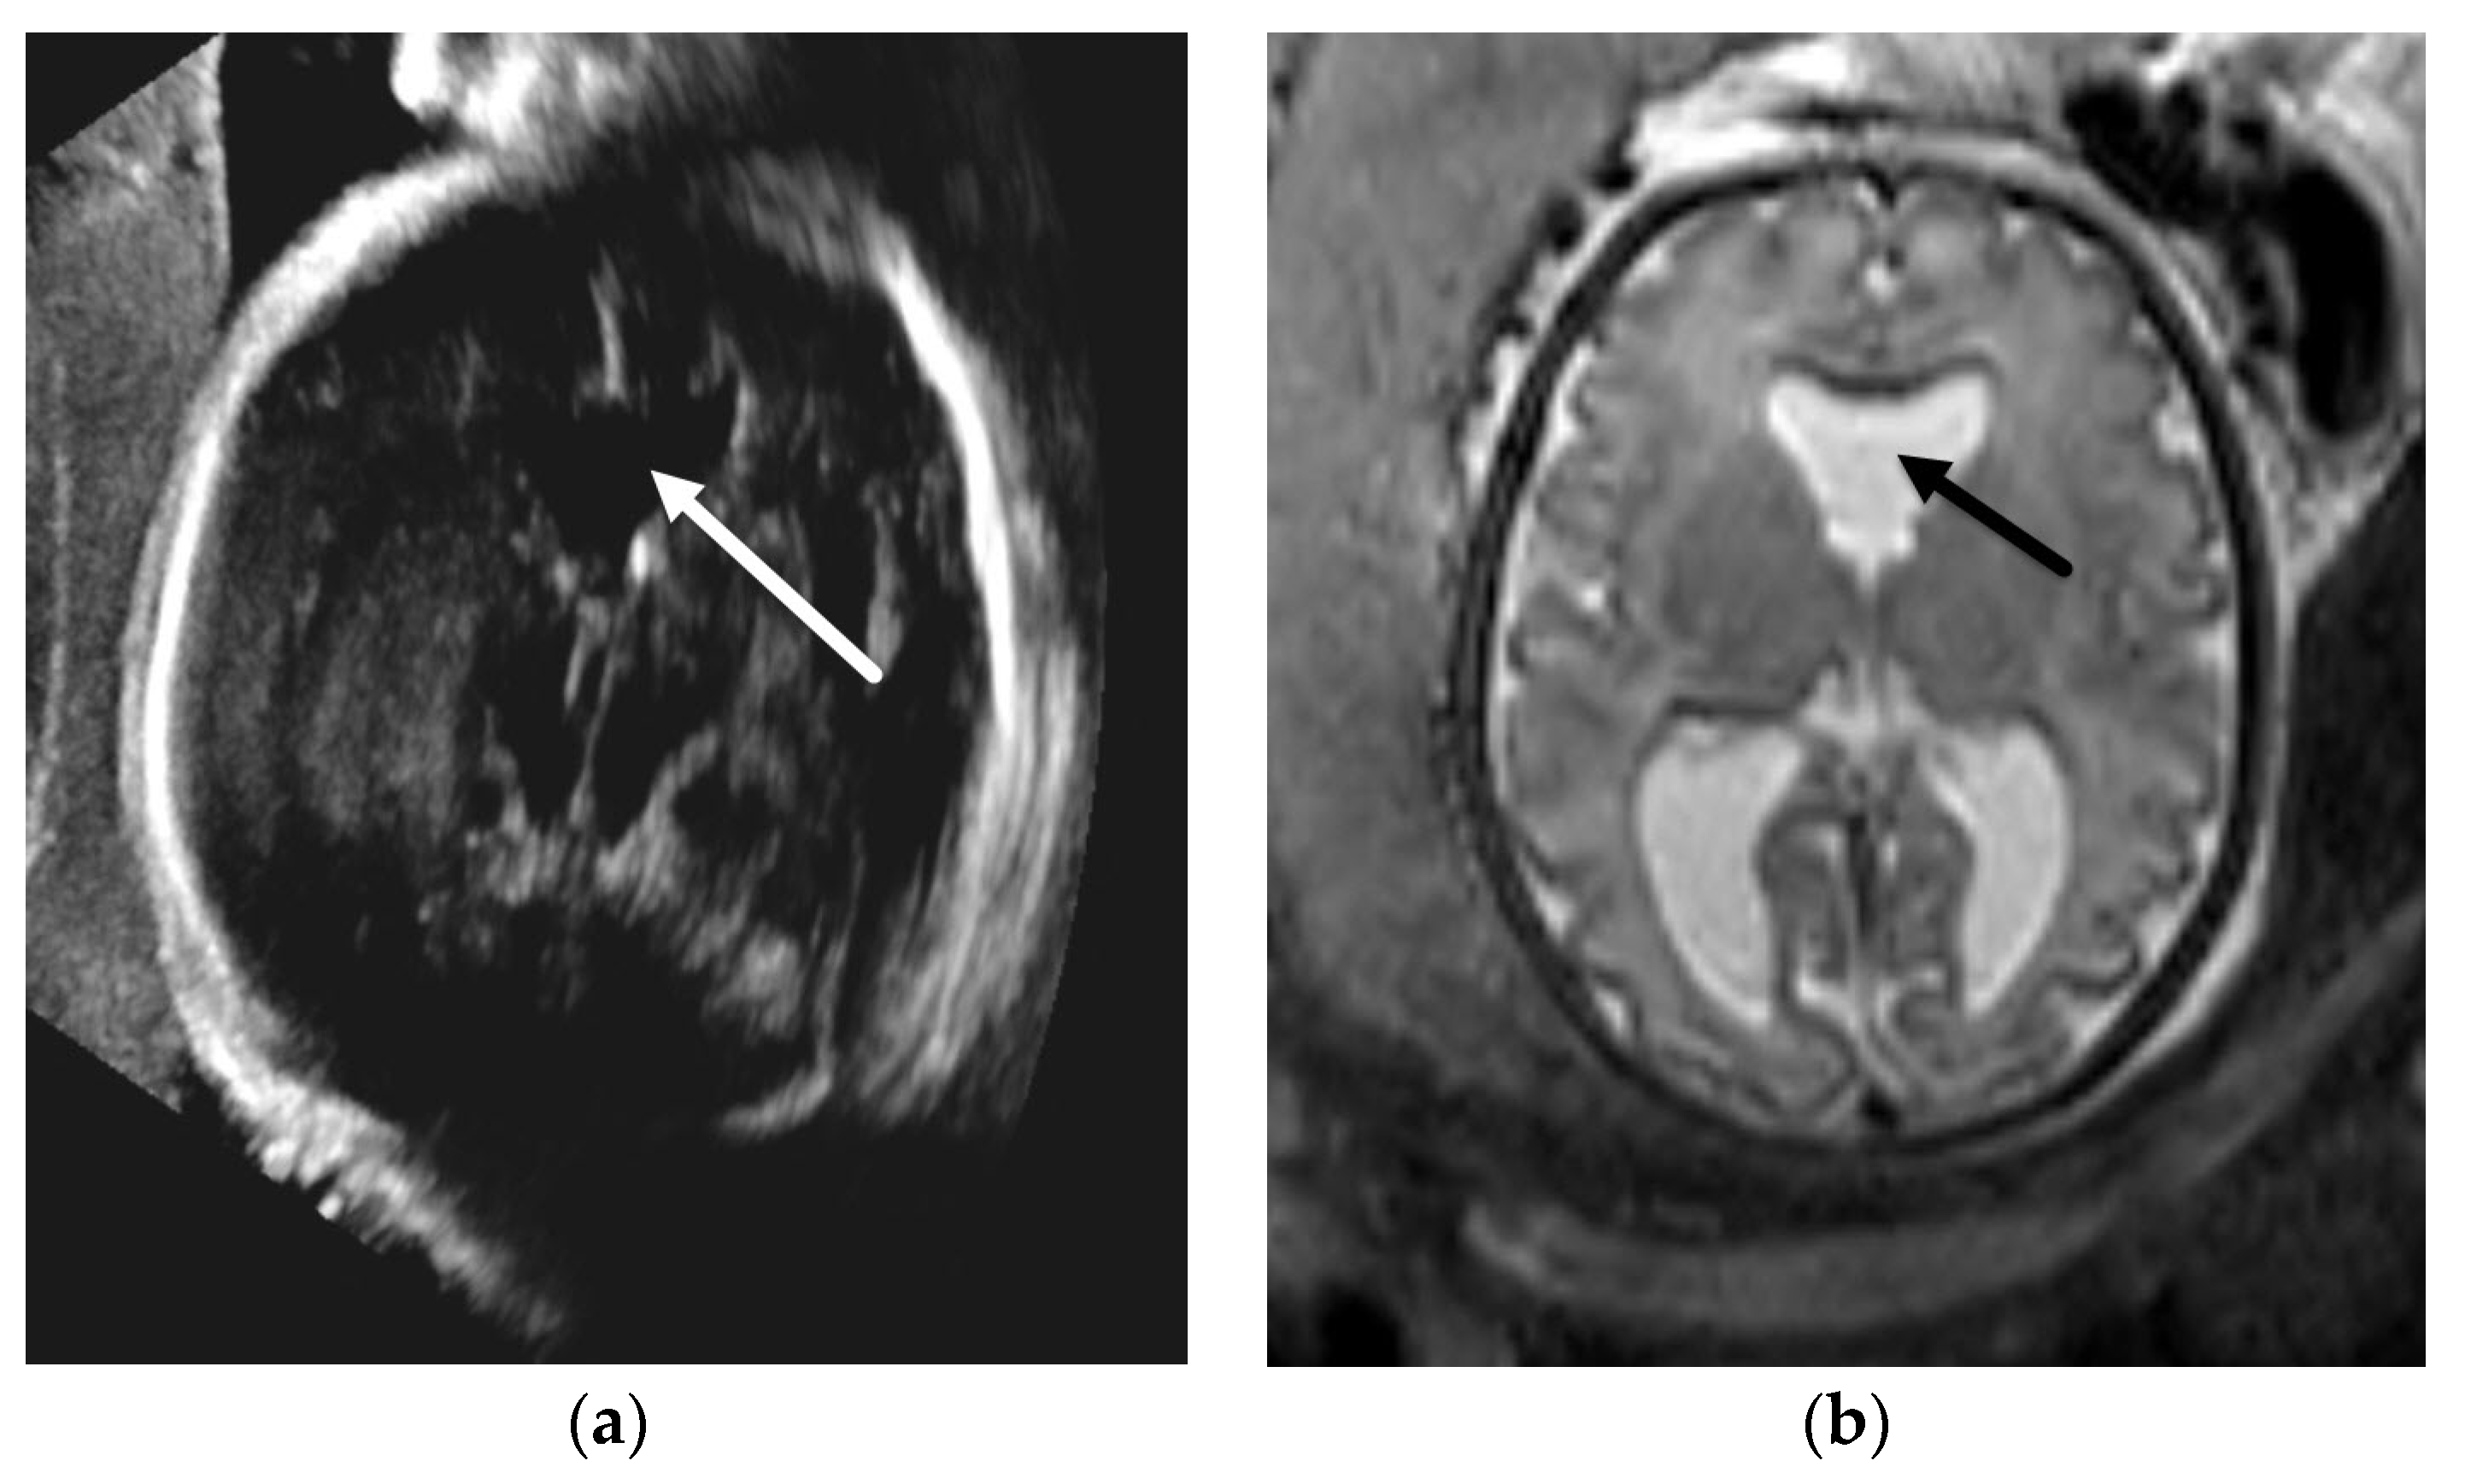

3.1.1. Aqueductal Stenosis

- Heaphy-Henault, K.; Guimaraes, C.; Mehollin-Ray, A.; Cassady, C.I.; Zhang, W.; Desai, N.K.; Paldino, M.J. Congenital aqueductal stenosis: Findings at fetal MRI that accurately predict a postnatal diagnosis. Am. J. Neuroradiol. 2018, 39, 942–948. [Google Scholar] [CrossRef] [PubMed] [Green Version]

- Kline-Fath, B.M.; Arroyo, M.S.; Calvo-Garcia, M.A.; Horn, P.S.; Thomas, C. Prenatal aqueduct stenosis: Association with rhombencephalosynapsis and neonatal outcome. Prenat. Diagn. 2018, 38, 1028–1034. [Google Scholar] [CrossRef] [PubMed]